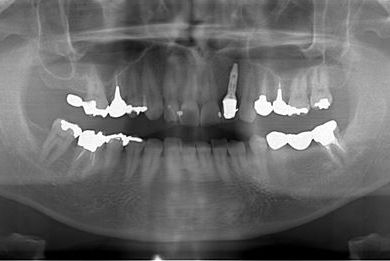

抜歯即日スピードインプラント治療

| 性別/年齢 | 男性 / 36歳 | ||||||||||||||||||||||||||||||||

| 主訴 | 前歯が折れていてないので、インプラント治療を希望。 | ||||||||||||||||||||||||||||||||

| 治療内容 | インプラント1本(抜歯即日スピードインプラント)、ハイブリッドセラミッククラウン1本 | ||||||||||||||||||||||||||||||||

| 総治療費 | 257,250円 | ||||||||||||||||||||||||||||||||

| 治療期間 | 7ヶ月 |